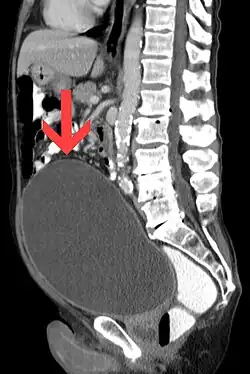

![]() Na CT snímku je patrné, že retence způsobila abnormální zvětšení močového měchýře | |

Retence moči, případně zadržení moči, či ischurie, je neschopnost jedince močit. Jedná se o běžnou komplikaci benigní hyperplazie prostaty (BPH), ačkoliv může být rovněž způsobena nervovou dysfunkcí, infekcí či léky (např. anticholinergiky, antidepresivy, inhibitory COX-2, amfetaminy a opiáty). Diagnóza a/nebo léčba může zahrnovat cévkování nebo prostatický stent.